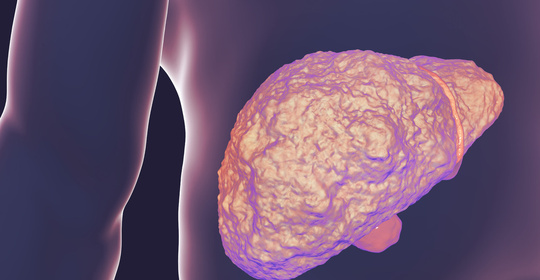

新生兒肝脾腫大:常見原因、評估與醫學指導